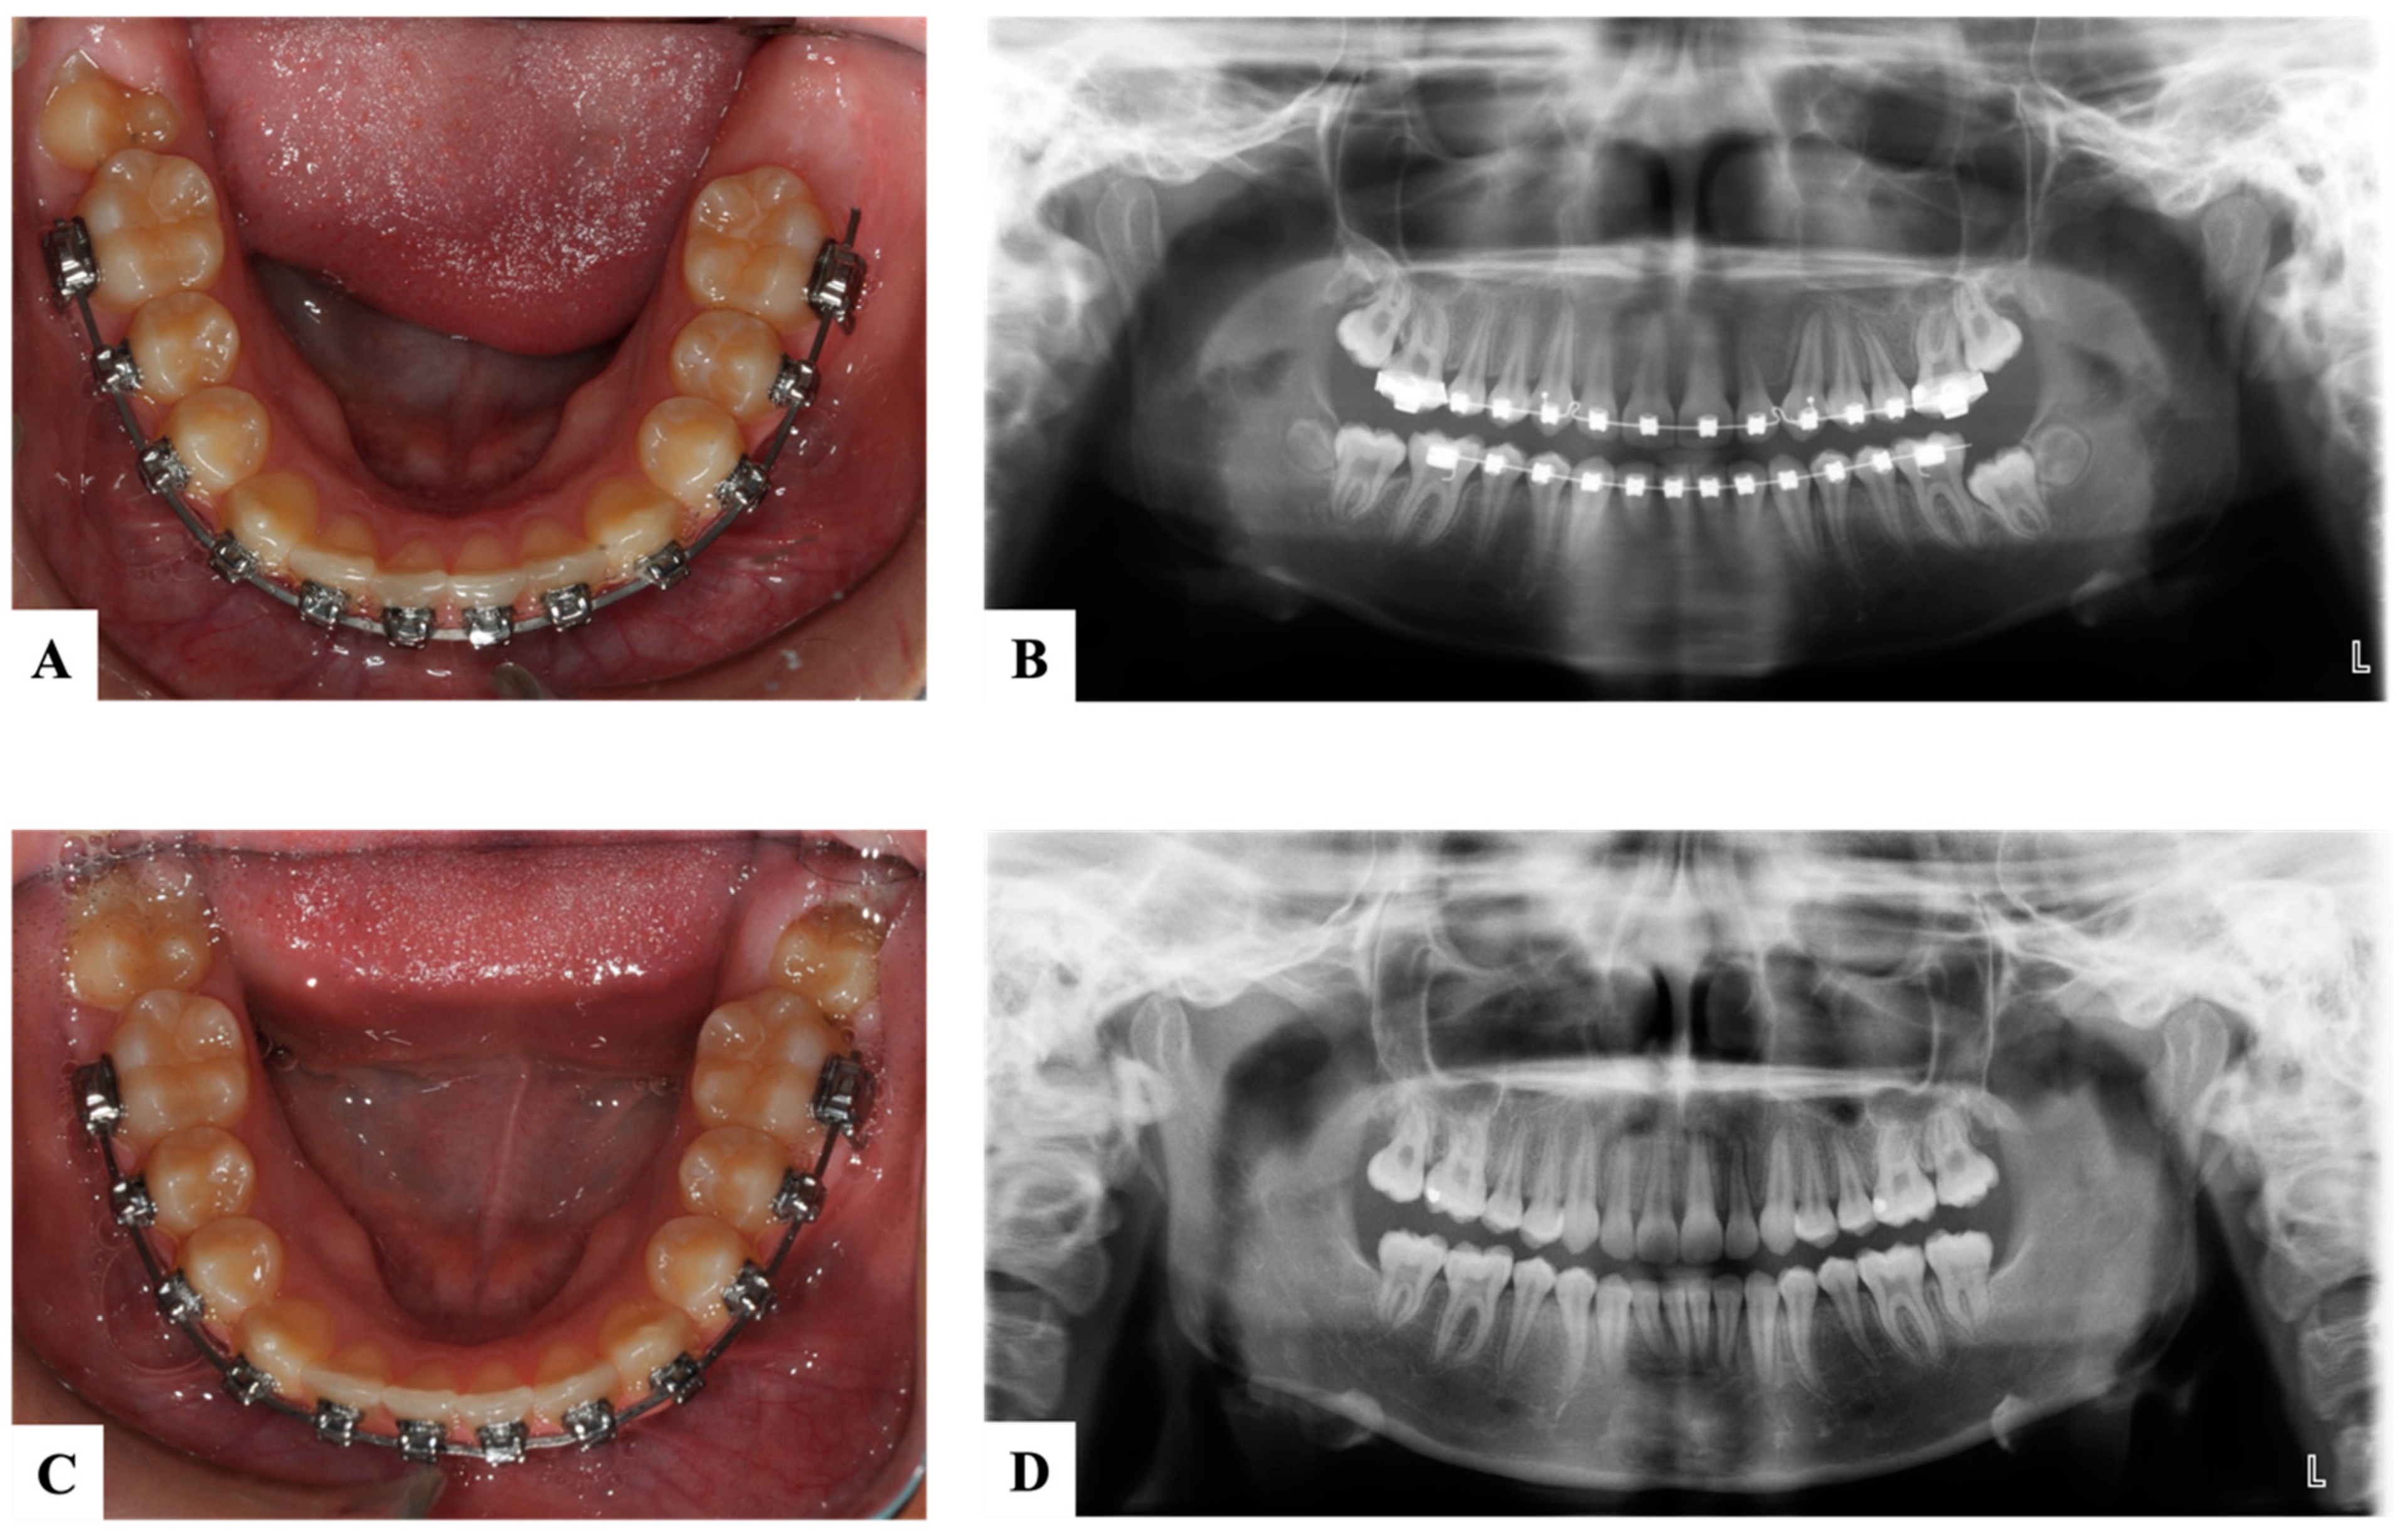

9. Ectopic First Permanent Molars

9.2. Distal Tipping

10. Ectopic Second Permanent Molars

11. Novel Devices

12. Maintenance